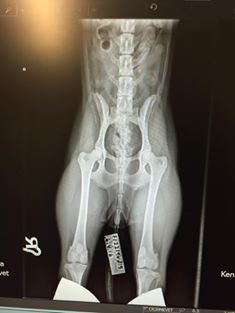

Kipaistiin keskiviikkona siispä Mevetiin. And looking good! Huh! Axelsson tuumasi lonkat A/A, kyynärät 0/0, polvet 0/0, silmät täysin terveet ja selkä normaali. Toki Kennelliitto tekee sitten lopulliset lausunnot, mutta kyllä näillä kelpaa liidellä. Tässä vielä puhelinräpsyt näytöltä:

![]() |

| Lonkat |